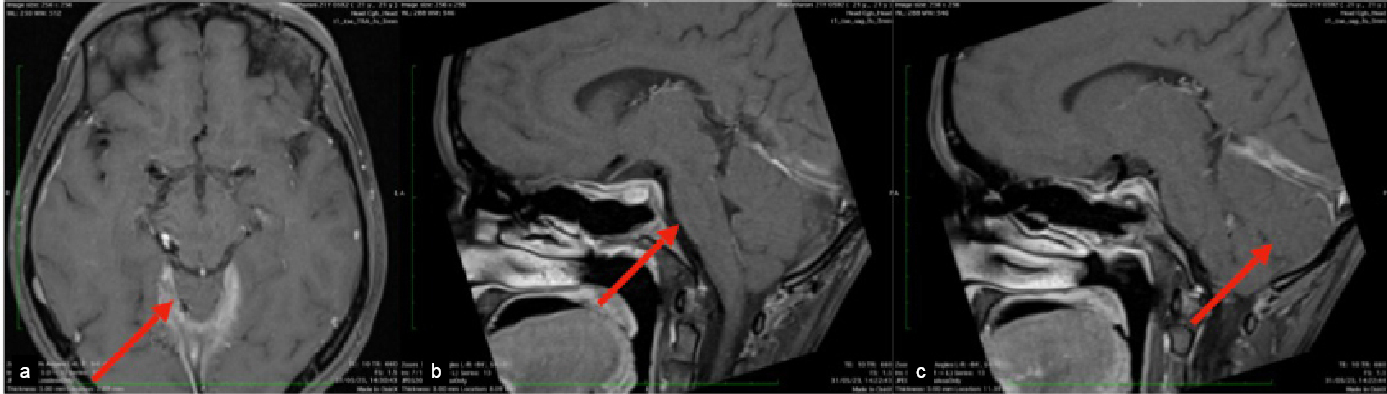

magnetic resonance imaging (MRI) brain with magnetic resonance venography (MRV)

revealed engorged dural spaces, enhancement of pachymeninges, flattening of

pons, sagging of bilateral tentorial and cerebellar tonsils (Fig. 4 a-c) with

thinning of both optic nerves complicated by chronic dural venous sinus

thrombosis.

Figure 4. MRI contrast axial-engorged dural venous sinus (a);

MRI sagittal contrast flattening of pons (b);and MRI sagittal

contrast herniation of cerebellar tonsils (c).